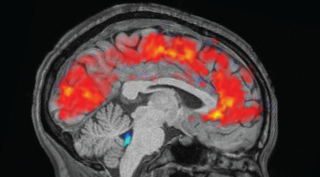

Sleep is a crucial physiological process that gives the body the opportunity to fully rest and rejuvenate itself. Humans spend around a third of their lives sleeping and yet many of us still fail to regularly catch those precious winks. Sleep deficiency can cause an array of physical and mental health problems, such as heart disease, high blood pressure, diabetes, stroke and depression. Discover what happens in the brain while you sleep, why some people need less sleep than others, whether white noise can help you sleep better and more in our latest articles below.

Study reveals why the brain 'zones out' when you're exhausted

Your sleep-deprived brain behaves as if you were about to nod off to sleep, even when you're awake.